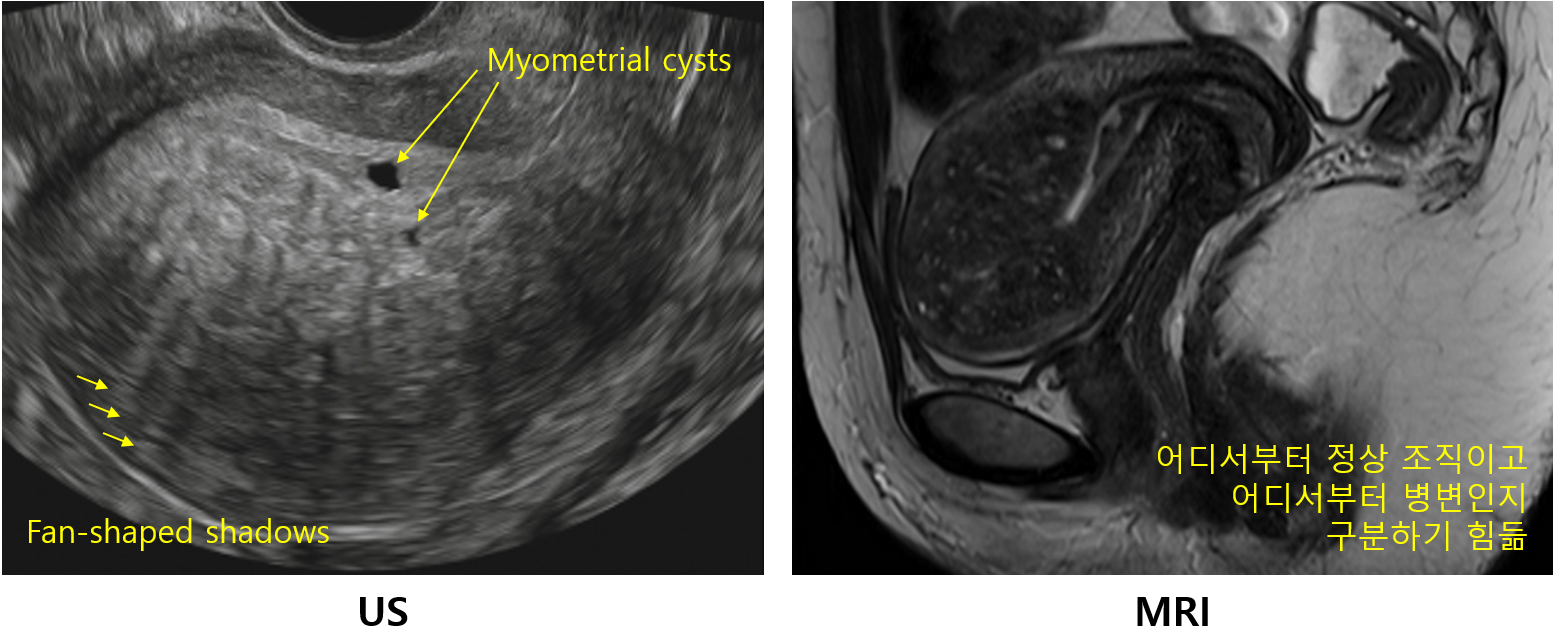

2) US

(1) 비대칭적인 자궁벽 두께 증가 및 자궁의 전반적인 비대

(2) 비균질한 에코: 고음영과 저음영이 섞여서 비균질함

• 자궁내막으로부터 사진 아래까지 고에코/저에코 선이 교차하면서 내려오는 양상을 흔히 나타냄 (fan-shaped shadows)

(3) 다발성 에코: 자궁근층 중간의 국소적 출혈(고에코), 낭종(저에코) 병변들이 다수 관찰됨

* 자궁샘근육증의 임상양상이 자궁근종과 비슷하기 때문에 US 사진을 보고 감별할 수 있어야 한다. 자궁근종이 독립적인 저에코 병변이라면, 자궁샘근육증은 혼합에코가 자궁 전체에 퍼져있는 소견이다.

3) MRI: 비대칭적인 자궁벽 두께 증가, 다발성 출혈 낭종